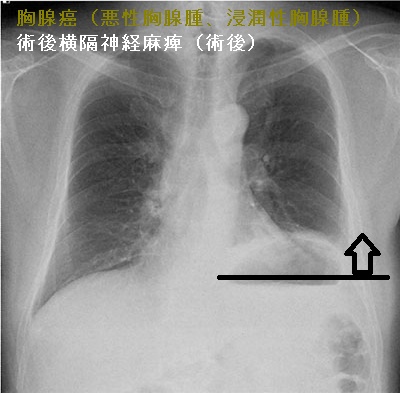

胸腺癌(悪性胸腺腫、浸潤性胸腺腫)

胸腺癌(悪性胸腺腫、浸潤性胸腺腫)は非常に稀で、標準的な治療が存在しません。組織型も、扁平上皮癌・未分化癌・小細胞癌と多様です。甲状腺機能亢進症/バセドウ病に合併した

胸腺癌(悪性胸腺腫、浸潤性胸腺腫)は前胸部から肺門部まで浸潤し、横隔神経自体にも浸潤するため、摘出手術で横隔神経を損傷する可能性が高い(術後横隔神経麻痺)。術後横隔神経麻痺では、術後から息が深く吸えなくなります。内肋間筋・補助呼吸筋と代償性の呼吸数増加で補える場合が多いが、重症例は胸腔鏡下横隔膜縫縮術の適応。